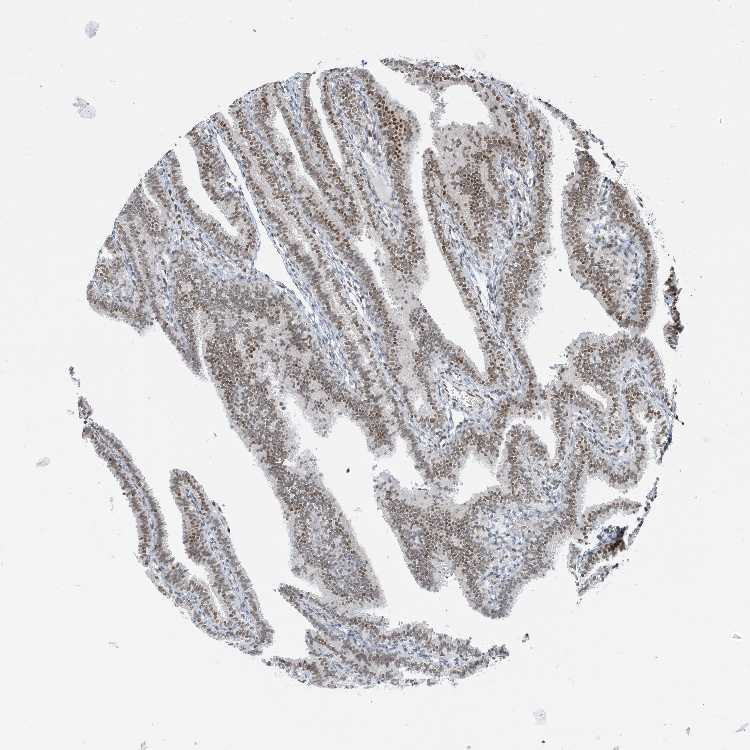

FALLOPIAN TUBE - Antibody stainingi

Antibody staining in the annotated cell types in the current human tissue is reported as not detected, low, medium, or high, based on conventional immunohistochemistry profiling in selected tissues. This score is based on the combination of the staining intensity and fraction of stained cells.

Each image is clickable and will lead to virtual microscopy that enables deeper exploration of all samples and also displays staining intensity scores, fraction scores and subcellular localization as well as patient and tissue information for each sample.

Antibody HPA035428

Glandular cells Medium